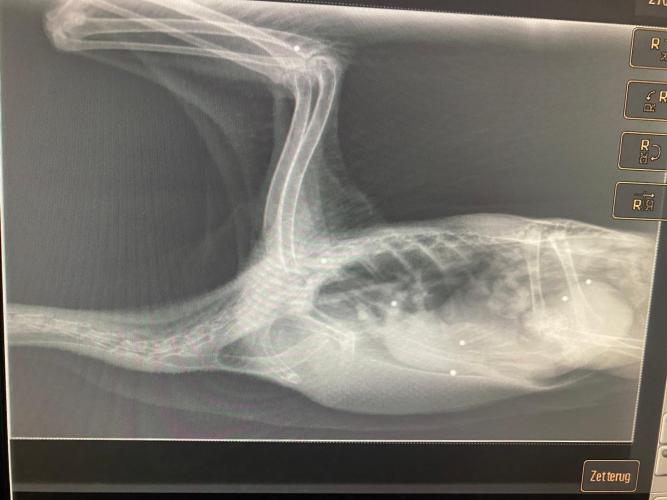

7 KOGELTJES IN ZIJN KLEINE LIJFJE

Appeltje wordt meegenomen naar de dierenarts, waar er röntgenfoto’s van hem worden gemaakt. De redders van Appeltje en de dierenarts schrikken wanneer ze tot de ontdekking komen dat er maar liefst 7 kogeltjes in zijn kleine lijfje zitten. Hij was doorzeefd met hagel, maar had het overleefd.

“We krijgen wel vaker jacht slachtoffers binnen. Wat we zien is dat ze, met name doordat ze keihard op de grond vallen nadat ze zijn aangeschoten, schade aan hun hoofd en hersenen oplopen. Dat verklaart ook het bloed aan de snavel”, vertelt de dierenarts. “De schade aan het hoofd kan ook hersenschade veroorzaken. Daarom loopt de gans wat slechter op zachte ondergrond.”

Volgens de dierenarts is er gelukkig kans op herstel voor Appeltje, omdat het al een stuk beter gaat met hem dan toen hij voor het eerst in de praktijk kwam. Vliegen gaat lastiger worden, omdat er ook een kogeltje in zijn vleugel zit.

“Ik zie wel 7 kogeltjes op de foto, verspreid over meerdere gewrichten en organen van de gans, waardoor de schade vrij groot is. Dat is niet te vergelijken met bijvoorbeeld een schot hagel in het been van een mens”, verklaart de arts.